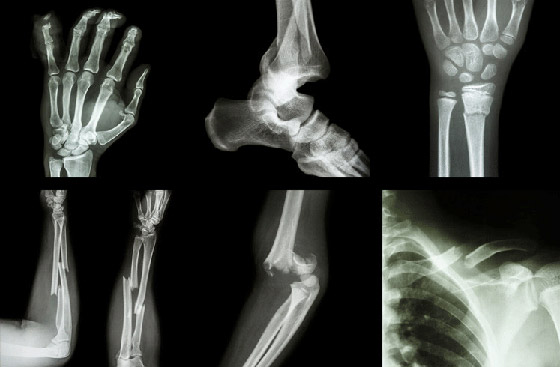

الكسور، على عكس ما يعتقد البعض، قد لا تسبب آلاما مبرحة في بعض الأحيان، وقد لا تعوقك عن الحركة. وفي هذا المقال، تفند كلوديا هاموند بعض المعتقدات الخاطئة حول كسور العظام.

أول سؤال سيطرحه عليك الآخرون إذا كنت تتلوى من الألم بعد ارتطام إصبع قدمك بعنف بشيء صلب هو: "هل تستطيع تحريكه؟ إن كنت تحركه فهو ليس مكسورا". لكن في الحقيقة، قد تستطيع أحيانا تحريك العظام المكسورة. ولهذا فإن القدرة على تحريك موضع الكسر في حد ذاتها ليست واحدة من المؤشرات الدالة على وجود كسر من عدمه، إذ تتضمن أهم ثلاثة أعراض للكسر، الألم والتورم وتغير شكل العظام. ولا شك أن بروز العظام بنحو 90 درجة أو اختراقها للجلد من العلامات التي تؤكد الإصابة بالكسر. وثمة علامة أخرى، وهي أن يحدث الكسر أثناء وقوعه صوتا مسموعا يشبه صوت طقطقة الأصابع.

2. إذا كنت مصابا بكسر، كنت ستشعر بألم حاد

ليس بالضرورة، طالما سمعنا حكايات عن أشخاص اختل توازنهم وسقطوا أرضا ثم عادوا في نفس اليوم إلى ممارسة أنشطتهم اليومية المعتادة من تزحلق على الجليد أو مشي أو حتى رقص، دون أن يدركوا أنهم أصيبوا بكسر. صحيح أن الكسر يسبب ألما في المعتاد، وأحيانا يكون مبرحا، ولكن إذا كان الكسر بسيطا فقد لا تلاحظه. لكن بمجرد أن تكتشف أنك أصبت بكسر، يجدر بك أن تتوجه للطبيب المختص دون إبطاء، ليقوم بتثبيت العظام المكسورة في مكانها الصحيح بالجبائر المناسبة حتى تلتئم، وذلك لتلافي حدوث مضاعفات كالالتهابات أو التشوه الدائم للعظام في موضع الكسر.